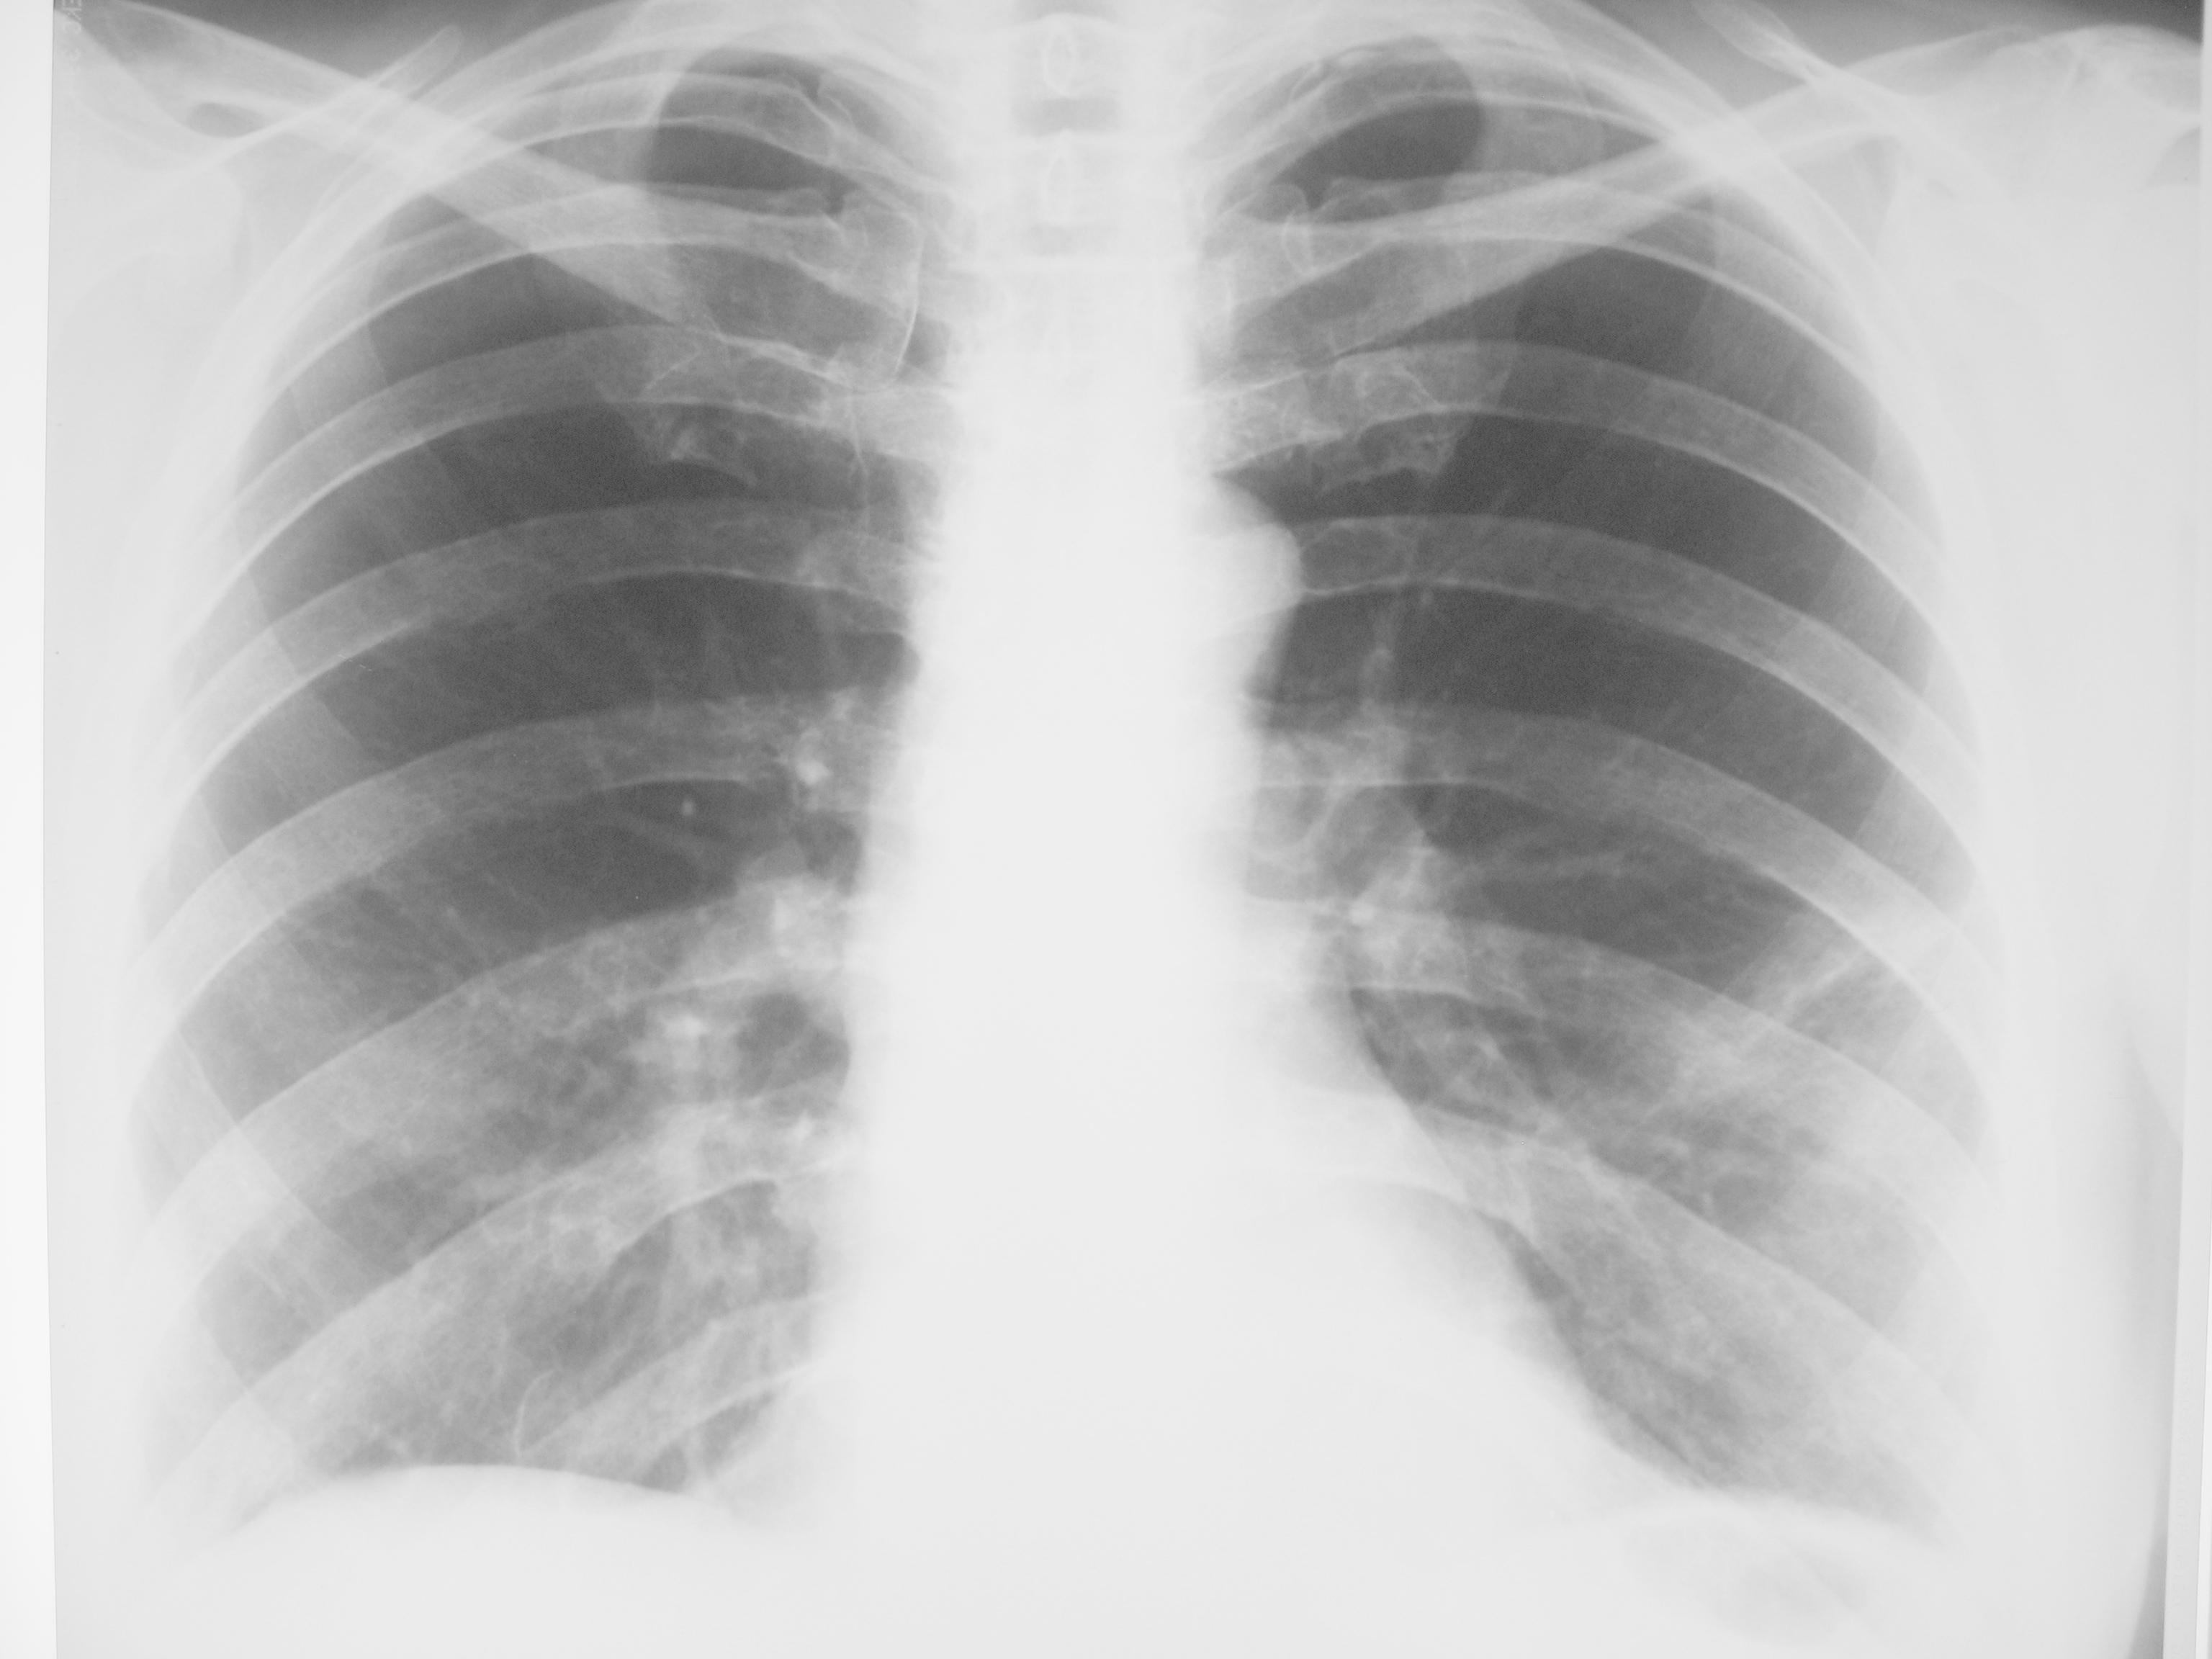

Пневмония? Локальный фиброз?

Пациентка около 65 лет с жалобами на слабость, повышение температуры в течение 2 дней направлена с д-зом ОРВИ. Пневмония?

Предыдущее исследование ОГК (ФЛГ) выполнялось в ноябре 2012 г

пусть будет пневмония, хотя на боковом не сыщешь )

Я бы написала в заключении очаговую пневмонию в S4.

По мне - так нет. Пневмосклероз, может дисковидный ателектаз.

Примерно так + локальное усиление легочного рисунка, уплотнение главной междолевой плевры.

Думаю, право на жизнь имеет версия двусторонней интерстициальной пневмонии. ОРВИ нижнего респираторного тракта.

Я за пневмонию, тем более на предыдущих флюорограммах чисто. На СКТ явно картина будет похлеще. Пусть лечится человек.

Сегодняшние снимки

img_2738.jpgimg_2739.jpg